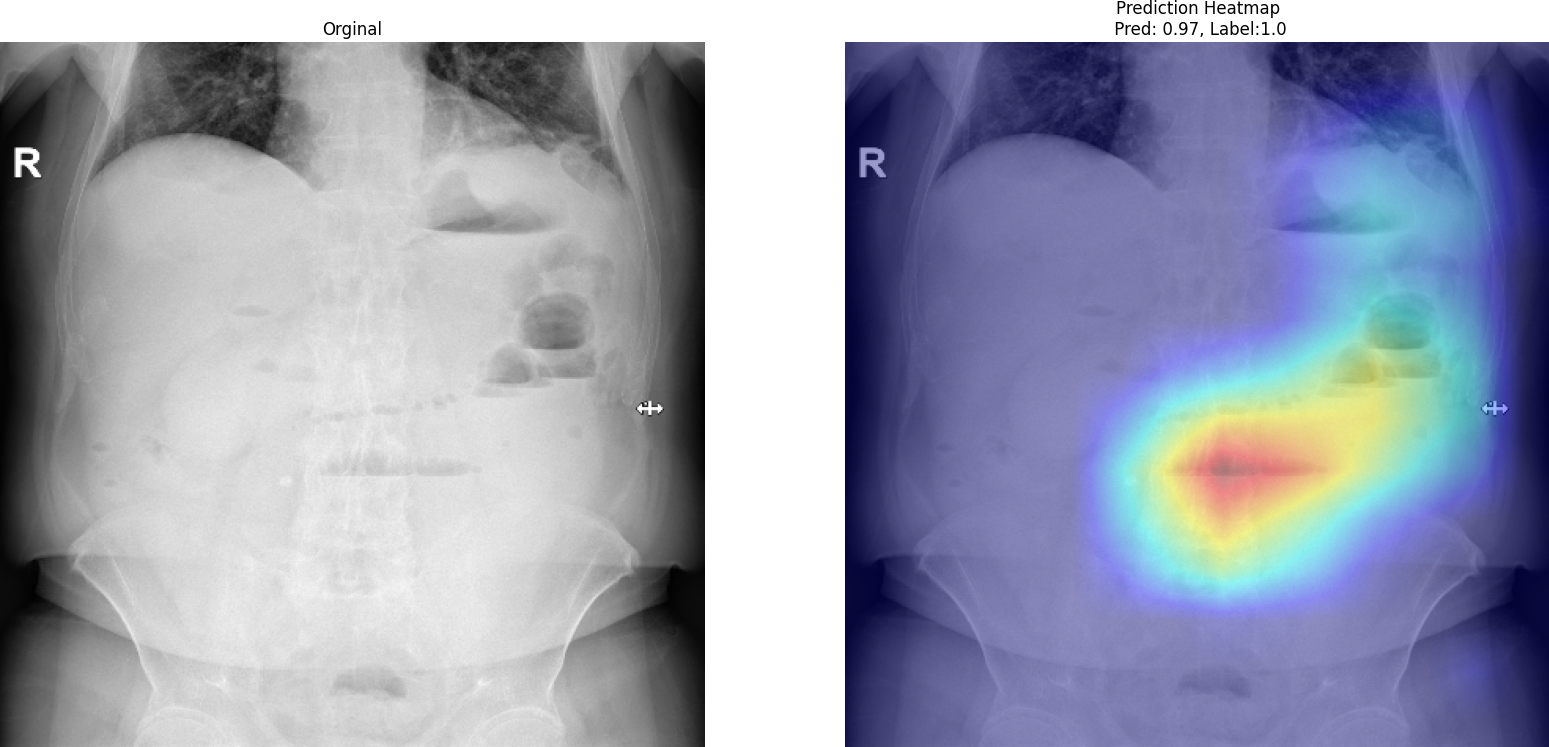

Grad-CAM visualization for MedViT

Grad-CAM visualization for MedViT highlighting diagnostically relevant regions.

As shown in the Grad-CAM visualization, the model focuses on meaningful anatomical regions rather than irrelevant background areas. The highlighted regions correspond to gas distribution patterns and abdominal structures that are clinically associated with obstruction. This behavior suggests that MedViT does not rely on spurious correlations but instead learns medically relevant features. Such interpretability is essential for building trust in AI-assisted diagnosis, especially in high-stakes clinical environments.